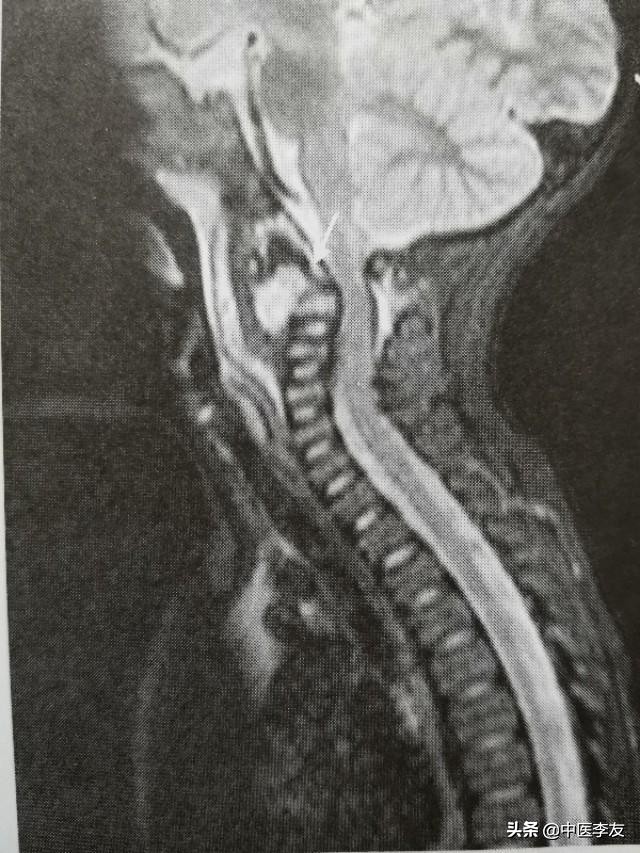

①颈椎:农业将突破椎体前方的骨膜和前中韧带废弃在颈长期以及其筋膜后方,第四颈椎以上可能形成咽后壁脓肿,第五颈椎以下可能形成食管后脓肿压迫喉头和食管,造成呼吸与吞咽困难。颈椎侧方病变的脓肿可出现在颈部两侧,或者沿着椎前的筋膜,以久斜方肌向锁骨上窝流窜。

3.MRI,表现是显示脊椎结核病灶和范围最敏感的方法,可发现椎体内早期炎性水肿。病灶T1WI表现为低信号,T2WI多表现为混杂高信号;GD-DTPA增强不均匀强化。脓肿和肉芽肿在T1WI上呈低信号,T2WI多为混杂高信号,部分均匀高信号,增强检查肉芽肿不均匀,均匀强化,脓肿壁薄且均匀的环状强化。

④冷性脓肿:腰椎结核可形成腰大肌脓肿,表现为腰大肌呈弧形向外突出高密度影,胸椎结核形成椎旁脓肿,表现为胸椎两旁梭形软组织肿胀高密度影,颈椎结核形成咽后壁脓肿,表现为咽后壁软组织影增宽,并呈弧形前突,较长时间的冷性脓肿可有不规则钙化。